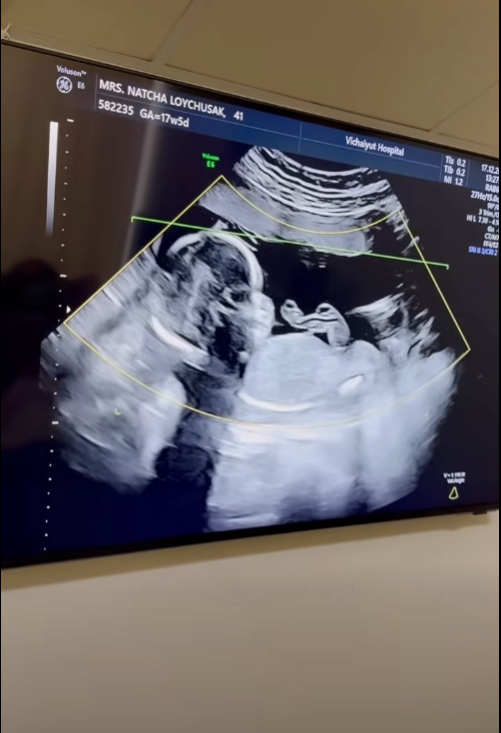

เรียกได้ว่าเป็นช่วงเวลาแห่งความสุขแบบคูณสองของครอบครัว "ลอยชูศักดิ์" เลยทีเดียว เมื่อคุณแม่คนสวยอย่าง "ครูก้อย นัชชา ลอยชูศักดิ์" ภรรยาสุดที่รักของ "เจมส์ เรืองศักดิ์ ลอยชูศักดิ์" ออกมาอัปเดตการตั้งครรภ์โชว์ท้องที่เริ่มป่องอย่างเห็นได้ชัด หลังตั้งครรภ์ลูกสาวคนที่สองได้ 17 สัปดาห์ พร้อมโชว์ภาพอัลตราซาวด์ที่เผยให้เห็นว่าเบบี๋ตัวยาวสมบูรณ์สุดๆ แถมมีแววจะตัวสูงตามรอยพี่สาวอย่าง "น้องเมดา" มาติดๆ

งานนี้คนที่ตื่นเต้นไม่แพ้พ่อแม่ก็คือ "น้องเมดา" ที่ตอนนี้กลายเป็นผู้ช่วยมือหนึ่ง ดูแลคุณแม่เป็นอย่างดี แถมยังเป็นคนรีเควสต์อยากมีน้องเอง หลังจากเห็นเพื่อนๆ ที่โรงเรียนมีพี่น้องกันหมด โดยเจมส์เล่าว่า พยายามให้ลูกสาวอยู่ในทุกช่วงเวลาสำคัญ ไม่ว่าจะไปพบคุณหมอหรือตอนอัลตราซาวด์ เพื่อให้เขาเกิดความผูกพันและมีส่วนร่วม เพราะบางครั้งเด็กในวัยนี้อาจเข้าใจผิดได้ว่าแม่จะแบ่งปันความรักให้น้องมากกว่าเขา แต่ตอนนี้เขารู้สึกว่าตัวเองเป็นส่วนหนึ่งของการมาของน้อง ทำให้เขารักและอยากช่วยดูแลน้องตั้งแต่อยู่ในท้อง